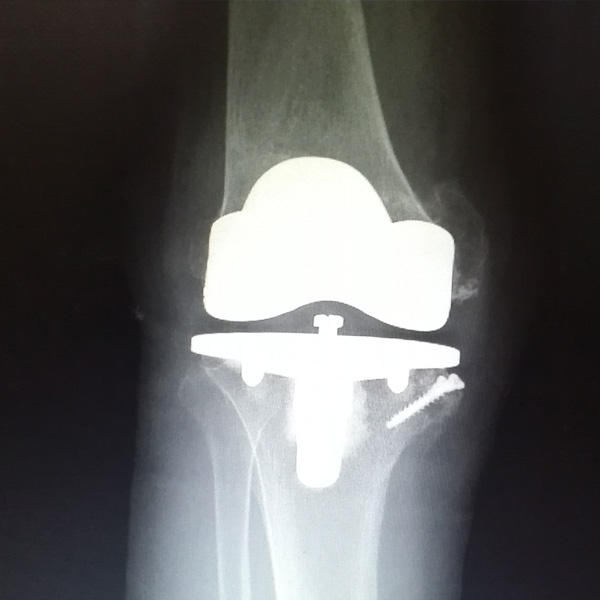

• 骨肉瘤手術骨肉瘤手術手術后手術前

骨肉瘤手術

患者張某,女,14歲,診斷為“左股骨遠端骨肉瘤”,當地醫院因為醫療技術和能力的限制,只能考慮截肢手術。患者家屬通過平臺推薦,指定到哈......